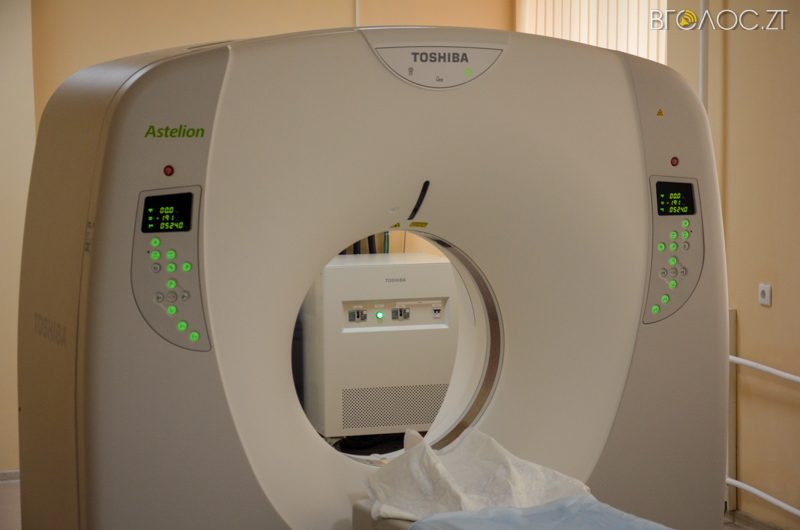

В обласній клінічній лікарні ім. О. Ф. Гербачевського відкрили роботу комунального комп’ютерного томографа 2016 року випуску, який обслуговуватиме пацієнтів щодня та цілодобово. Кошти на придбання обладнання виділили на сесії обласної ради у липні 2016 року. Комп’ютерний томограф є унікальним, оскільки робить сканування у 32 розрізах, водночас зменшує променеве навантаження на пацієнта.

«Такого комп’ютерного томографа ні у приватних, ні в комунальних установах немає. З його допомогою ми можемо забезпечити жителів нашої області високоякісною діагностикою та лікуванням», – розповів головний лікар обласної клінічної лікарні ім. О.Ф. Гербачевського Богдан Леськів.

Пройти безкоштовне обстеження на комп’ютерному томографі зможуть учасники АТО, чорнобильці, інваліди, онкохворі дорослі та діти. Інші пацієнти, які не належать до пільгових категорій, купуватимуть тільки витратні матеріали – плівку та рентген-контрасні речовини. Сама ж процедура буде безкоштовною.

На придбання томографа з обласного бюджету виділили 13 млн грн, з них понад 1 млн грн вдалося зекономити та придбати інше обладнання для лікарні.